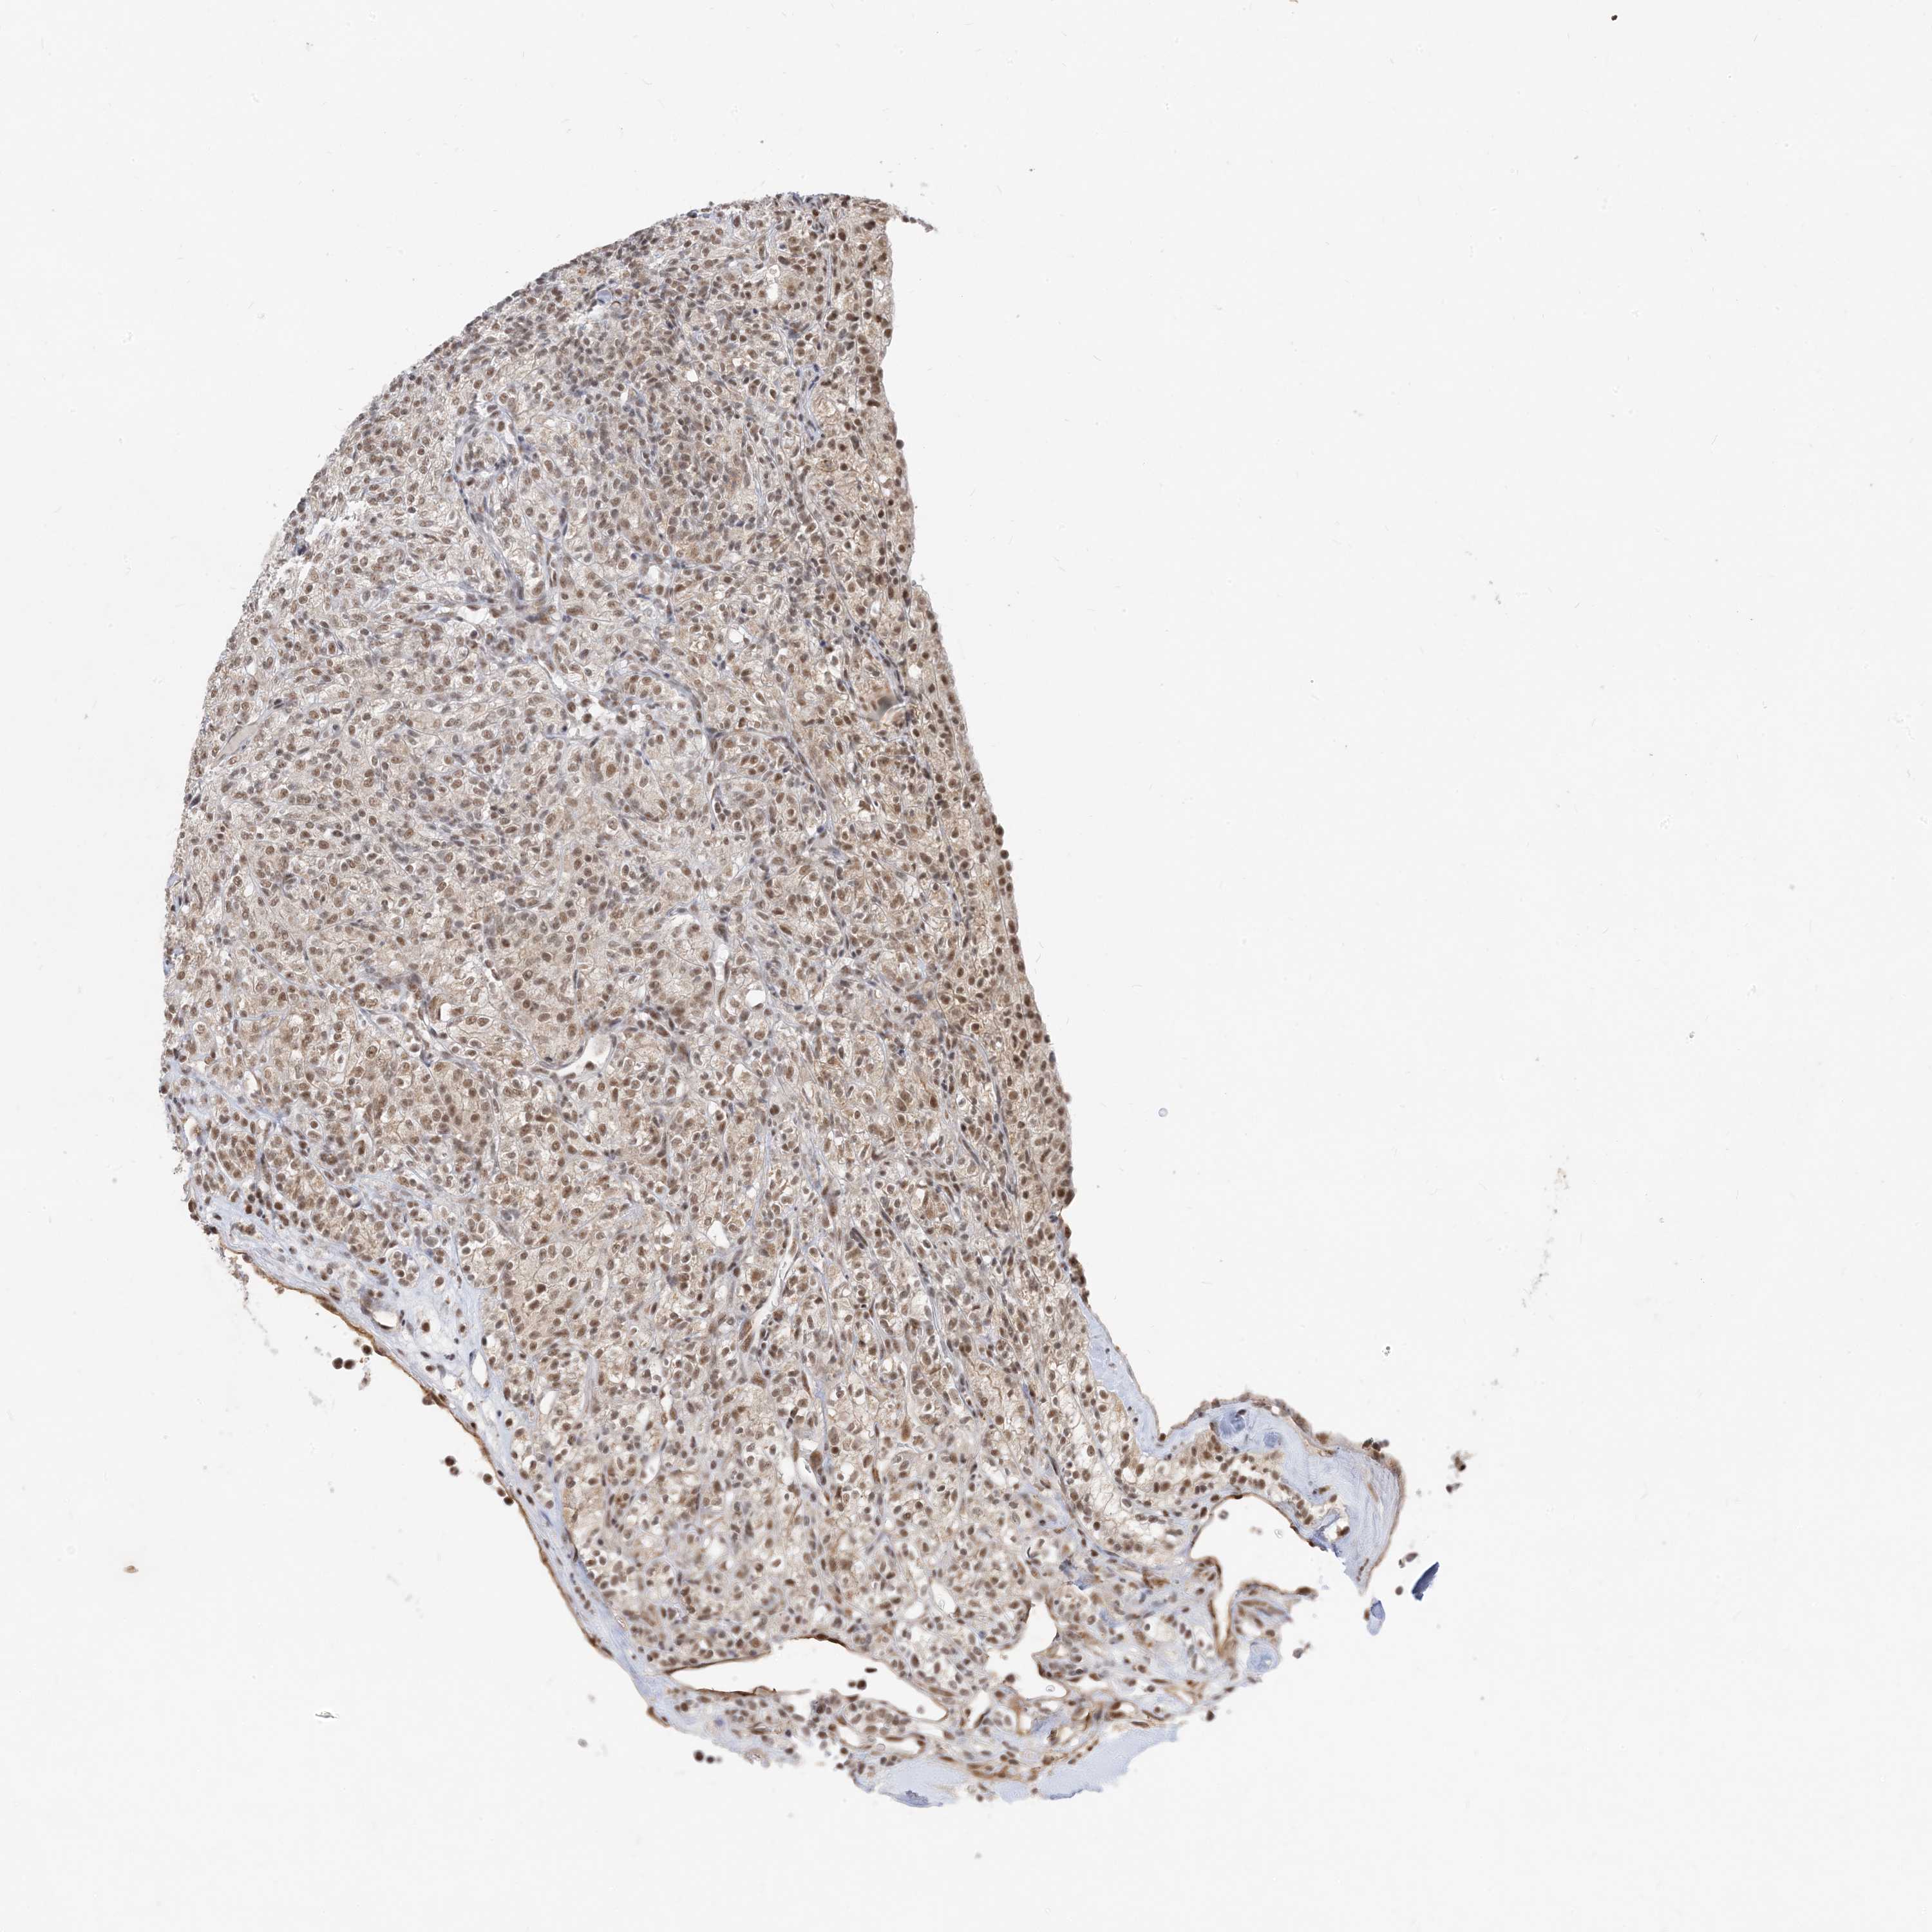

KIDNEY RENAL CLEAR CELL CARCINOMA (VALIDATION) - Interactive survival scatter ploti

The Survival Scatter plot shows the clinical status (i.e. dead or alive) for all individuals in the patient cohort, based on the same data that underlies the corresponding Kaplan-Meier plots. Patients that are alive at last time for follow-up are shown in blue and patients who have died during the study are shown in red.

The x-axis shows the expression levels (FPKM) of the investigated gene in the tumor tissue at the time of diagnosis. The y-axis shows the follow-up time after diagnosis (years). Both axes are complimented with kernel density curves demonstrating the data density over the axes. The top density plot shows the expression levels (FPKM) distribution among dead (red) and alive patients (blue). The right density plot shows the data density of the survived years of dead patients with high and low expression levels respectively, stratified using the cutoff indicated by the vertical dashed line through the Survival Scatter plot. This cutoff is automatically defined based on the FPKM cutoff that minimizes the p-score. The cutoff can be changed by dragging the vertical line or by entering a cutoff value in the square labeled "Current cut-off".

Under the Survival Scatter plot the p-score landscape (black curve; left axis) is shown together with dead median separation (red curve; right axis). Dead median separation is the difference in median mRNA expression between patients who have died with high and low expression, respectively. It is calculated as follows: median FPKM expression of dead patients with high expression - median FPKM expression of dead patients with low expression. This is intended to aid the user in visually exploring custom cutoffs and the associated p-scores and dead median separation.

Individual patient data is displayed and can be filtered by clicking on one or more of the category buttons on the top of the page. Categories describing expression level and patient information include: high, low, alive, dead, female, male and tumor stages. The scale of the x-axis can be toggled between linear and log-scale by clicking on the "x log" button. Mouse-over function shows TCGA ID, patient information and mRNA expression (FPKM) for each patient.

& Survival analysisi

Kaplan-Meier plots summarize results from analysis of correlation between mRNA expression level and patient survival. Patients were divided based on level of expression into one of the two groups "low" (under cut off) or "high" (over cut off). X-axis shows time for survival (years) and y-axis shows the probability of survival, where 1.0 corresponds to 100 percent.

SF3A3 is not prognostic in Kidney Renal Clear Cell Carcinoma (validation)

Best expression cut offi

: 37.08

Average pTPM 35.4

Number of samples 100